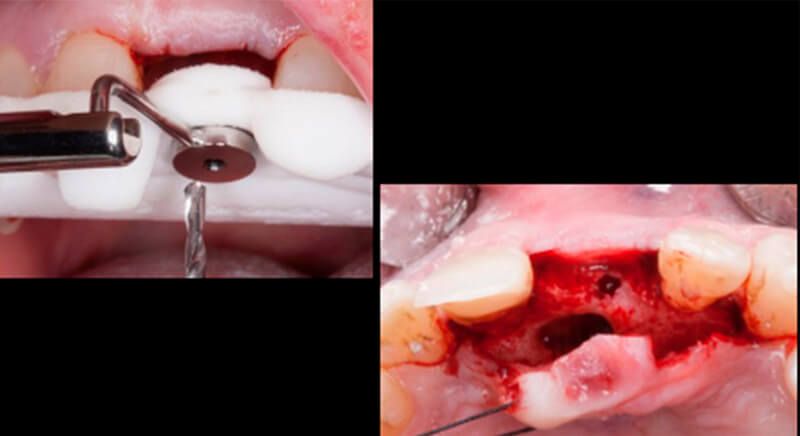

This information enabled us to rule out the option of surgery without a flap, as regeneration simultaneous to surgery would be needed, so the idea of using guided surgery was maintained.

The guided surgery was performed by lifting a full thickness mucoperiosteal flap. A Biomimetic Ocean CC implant, diameter 3.5mm and length 10mm, was inserted using the surgical guide in the ideal three-dimensional position and the defects were regenerated with xenograft and reabsorbable membrane, the nasopalatine duct on the palatine side and the area of dehiscence on the vestibular.

During the same surgical intervention, a short 3mm Avinent healing abutment was positioned and fully covered by the flap. Primary closure was completed and we waited 6 months for the bone graft to mature.